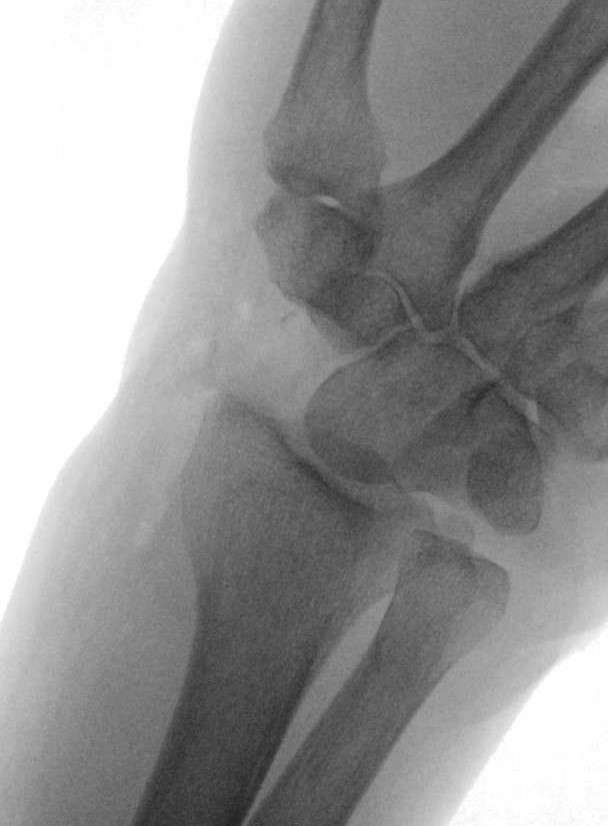

There was a visible deformity at the right wrist with bruising, and swelling. Additionally, a positive Hoffman-Tinel sign was observed with paresthesia in the median nerve area. A radiological examination of the hand was then performed, which revealed a dislocation of the scaphoid and lunate bones. No bone fractures were detected.

The surgical procedure involved exposing and splitting the 4th and 3rd extensor tendon compartments to facilitate access. The extensor pollicis longus (EPL) tendon was transposed subcutaneously, and the extensor tendons were luxated out of the 4th extensor tendon compartment. The posterior interosseous nerve was identified and divided. Additionally, the dorsal joint capsule was found to be torn, and the scaphoid and lunate bones were luxated ventrally, with the lunate bone rotated 90°

A skin incision was made along the Linea vitalis, extending proximally to the distal forearm. The palmar aponeurosis, flexor brevis muscle (which was coagulated), and the flexor retinaculum were divided. The median nerve was exposed and underwent neurolysis, and the palmar branch of the median nerve was also identified and neurolyzed. Both the median nerve and the flexor tendons were retracted to the side. The palmar joint capsule was found to be torn. The scaphoid and lunate bones were displaced into the carpal tunnel. A carpal tunnel release was performed. The lunate and scaphoid bones were only secured by the ventral ligaments. The remaining ligaments, including the SL and LT ligaments, were torn. The lunate and scaphoid bones were then resected from the palmar side.